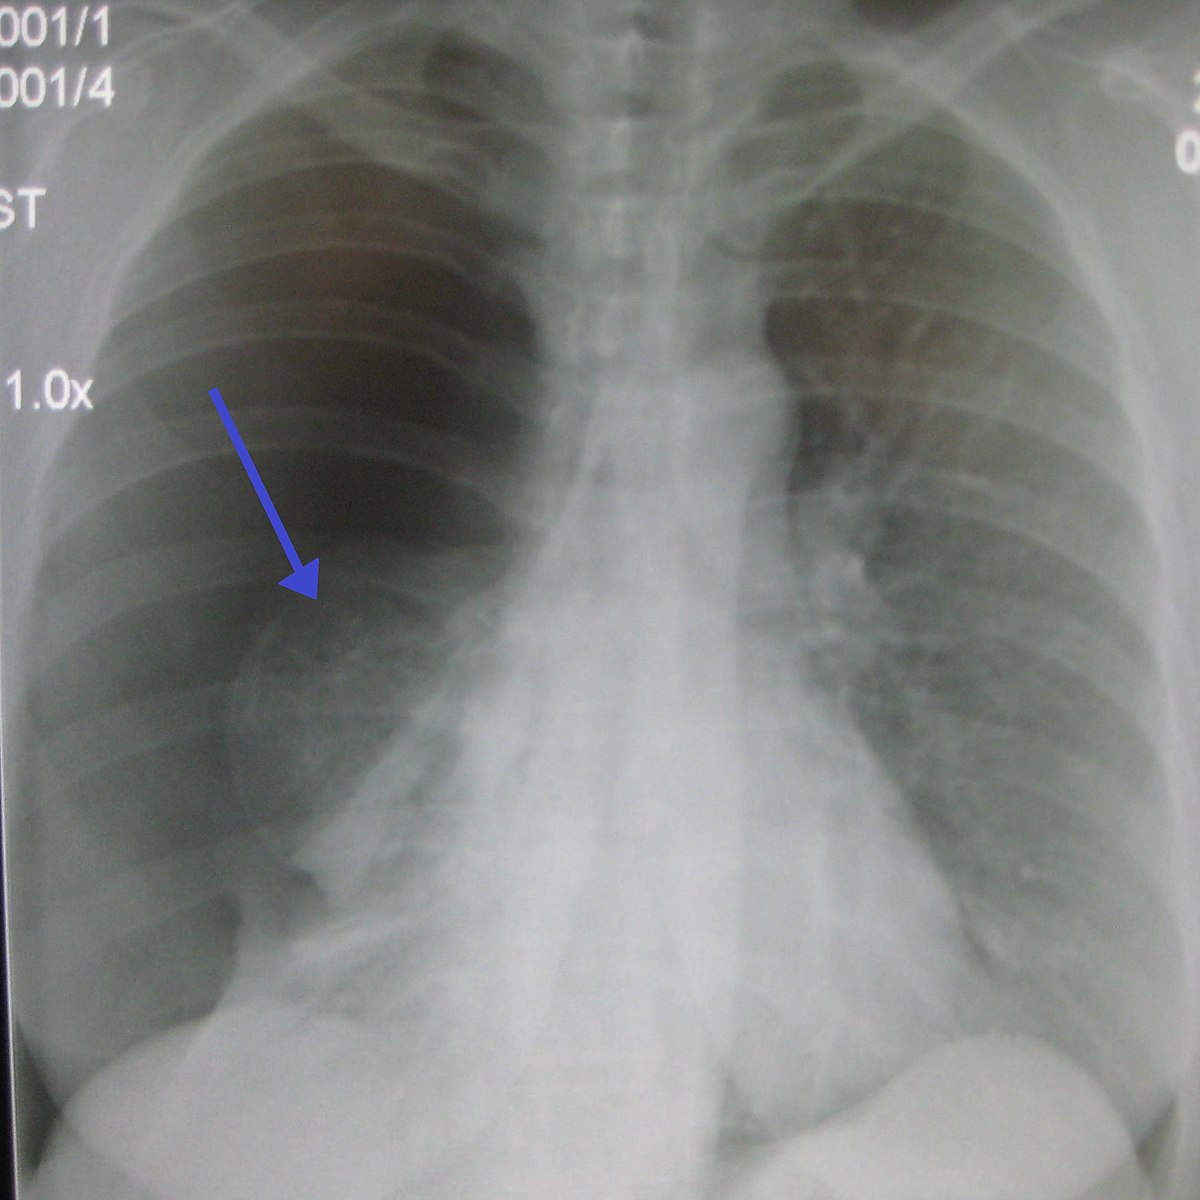

PA and lateral chest x-rays are the recommended investigation for initially diagnosing a pneumothorax. Usually, an outline of the collapsed lung can be seen alongside absent lung markings. Sometimes, the deep sulcus sign may be visible. This describes a costophrenic angle which appears more inferiorly deep than usual and is a sign of a pneumothorax.

The size of the rim of air between the lung margin and chest wall is measured at the level of the lung hilum. Anything greater than 2cm is defined as a large pneumothorax, with anything less being a small pneumothorax.

Right Sided Pneumothorax